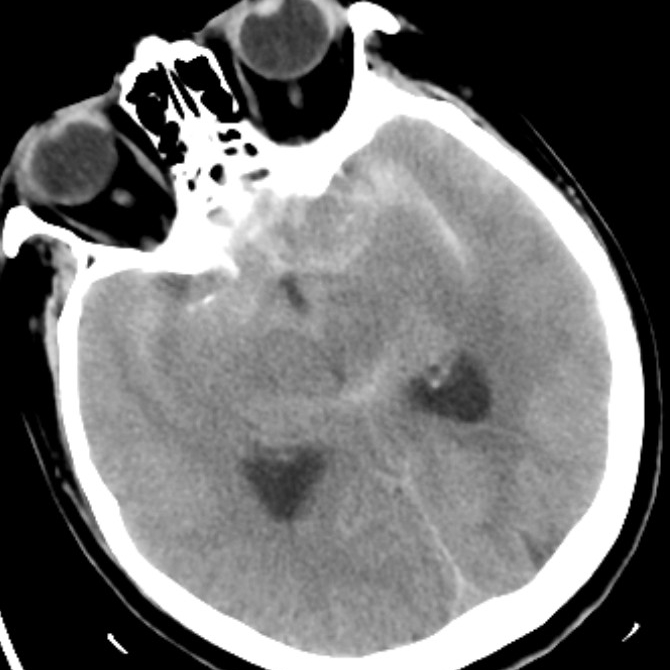

病例二为58岁女性患者。因“突发剧烈头痛伴呕吐3小时”就诊于清华大学附属垂杨柳医院急诊科,行头颅CT检查提示蛛网膜下腔出血。患者嗜睡,频繁呕吐,不排除颅内再出血。为争分夺秒抢救患者生命,神经外科脑血管病介入团队紧急为患者实施了DSA,显示左侧大脑中动脉分叉处宽颈动脉瘤,主要累及下干。术中采取双微导管技术,于动脉瘤内填塞弹簧圈,并置入一枚支架保证致密栓塞和下干分支血管的通畅。成功“拆弹”,化险为夷,患者恢复过程顺利,出院时无神经功能缺损。

▲头颅CT显示蛛网膜下腔出血

▲术后DSA显示动脉瘤致密栓塞,载瘤动脉通畅